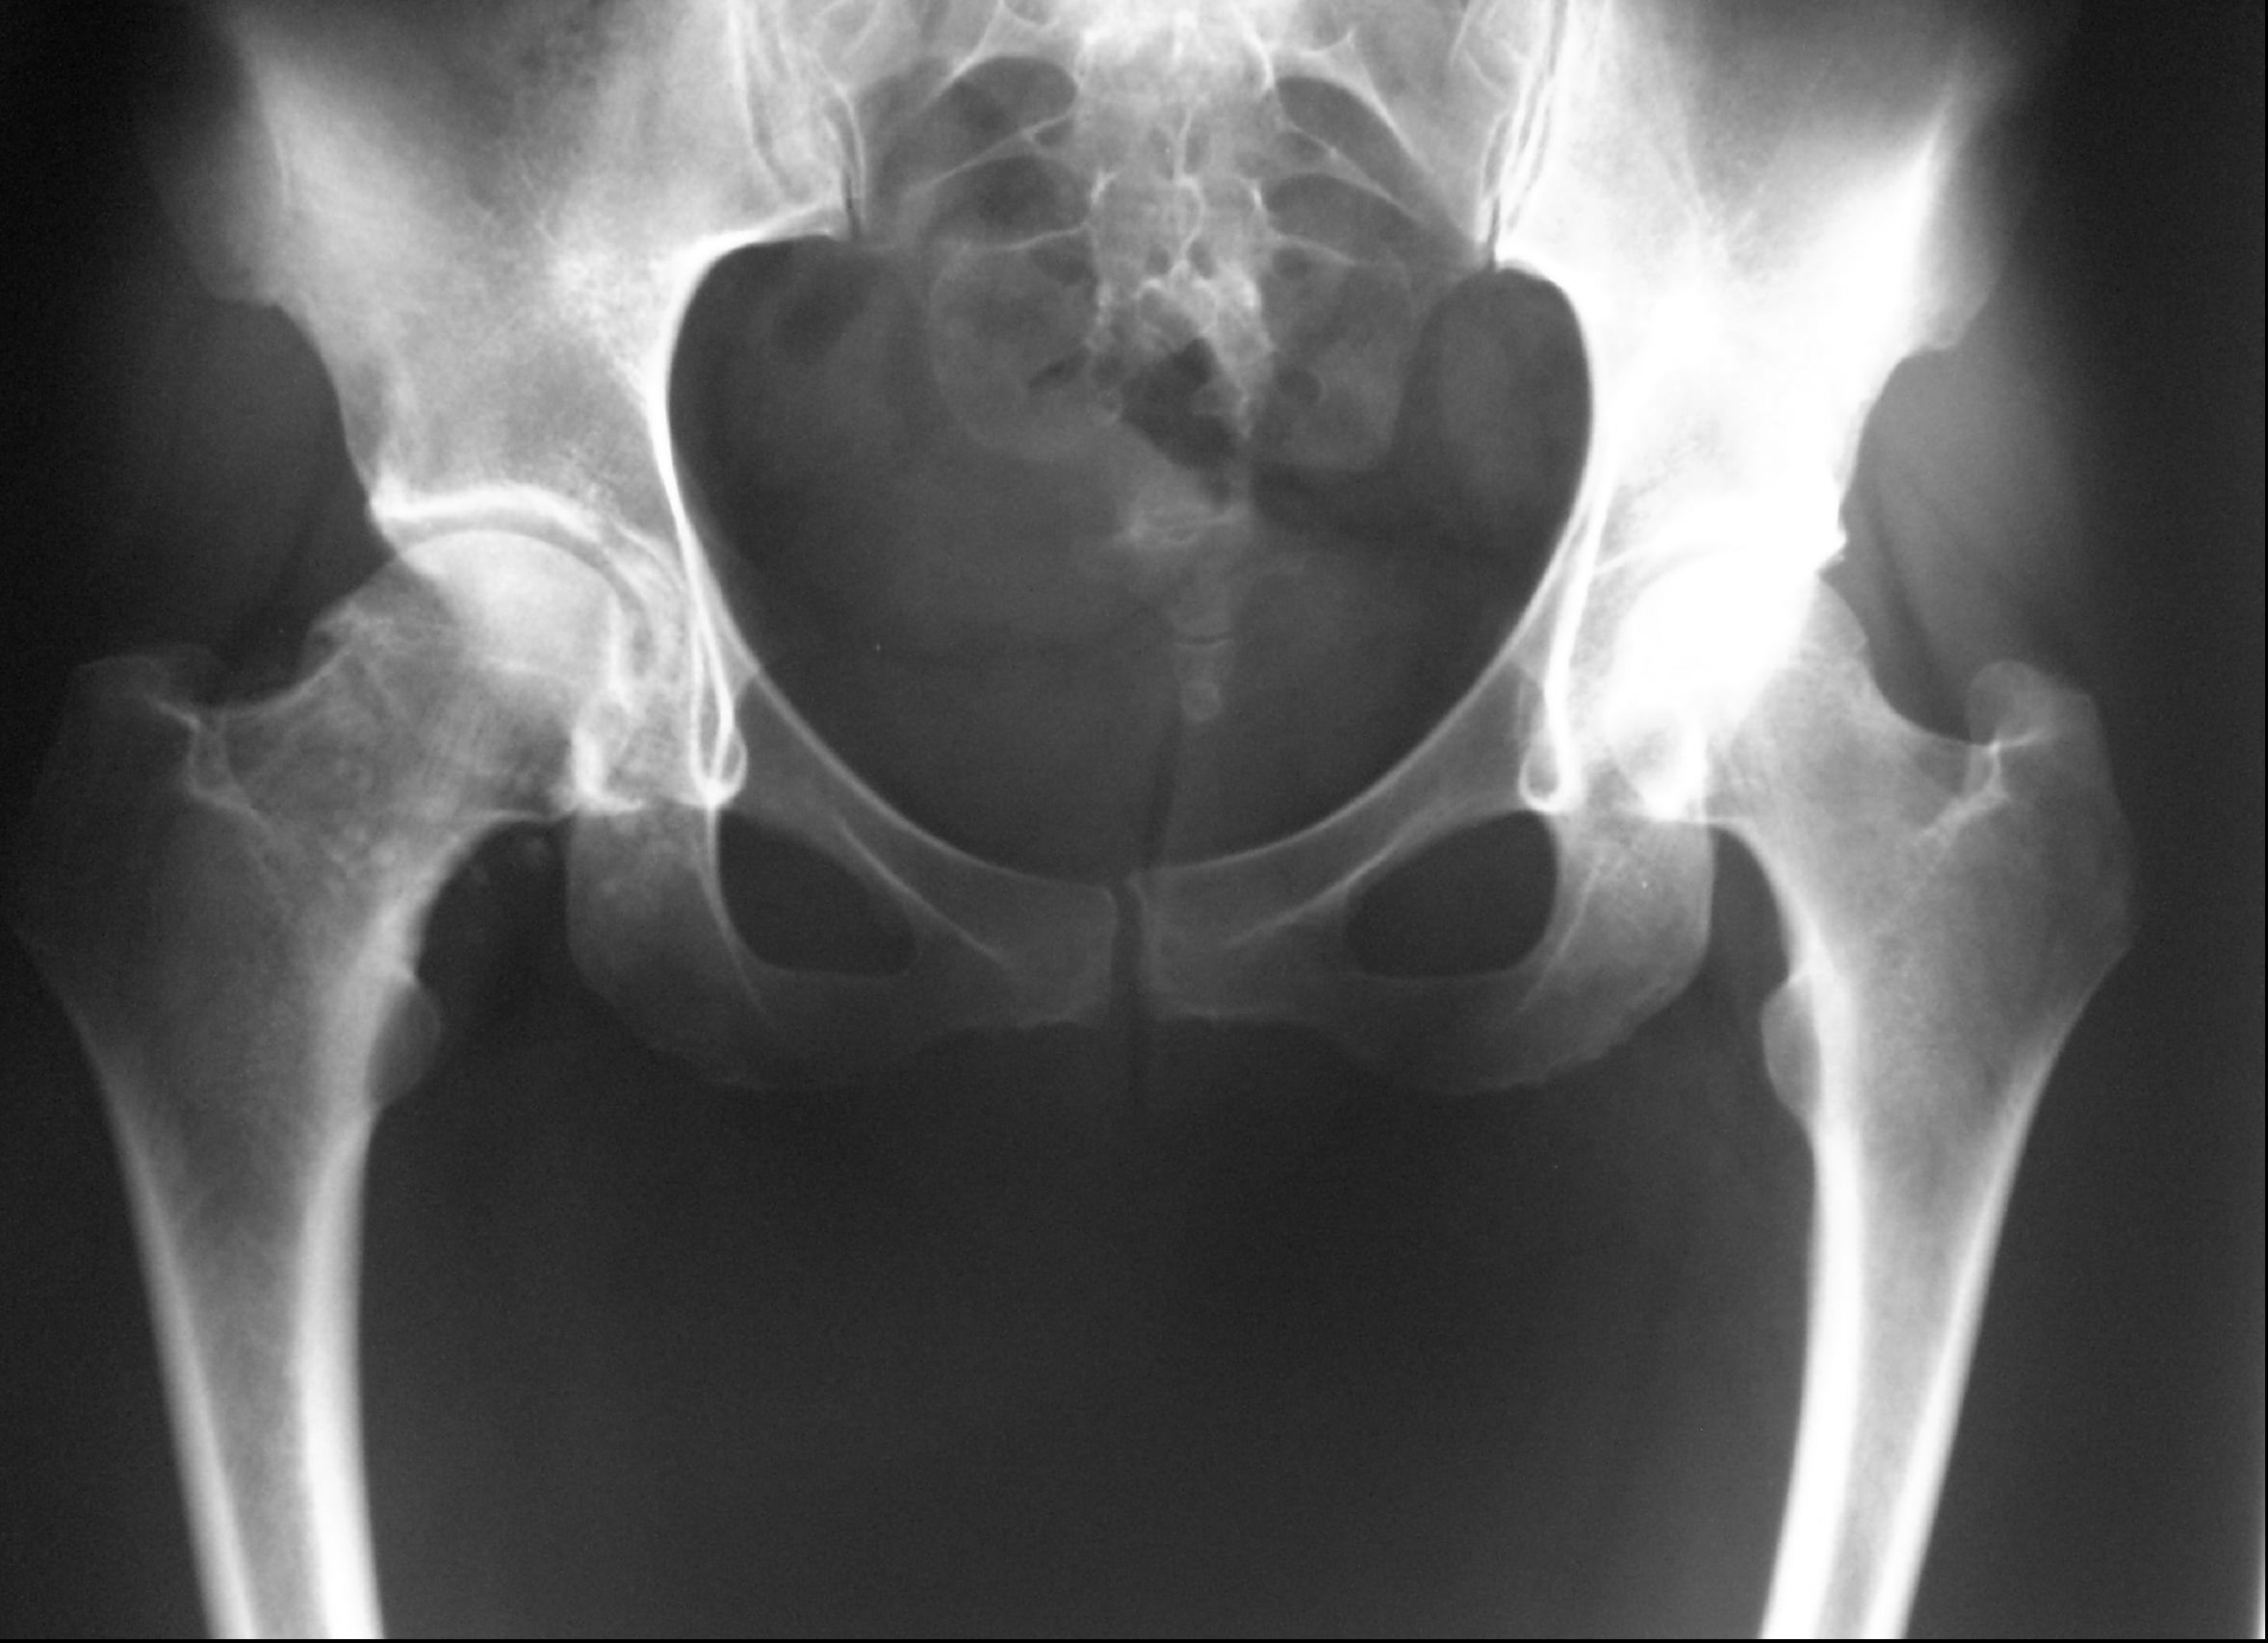

Introducción: La condromatosis sinovial se define como una lesión metaplásica benigna, de baja incidencia en cadera. La técnica ideal de tratamiento genera controversia por la probable recurrencia y la progresión degenerativa descrita para técnicas tanto a cielo abierto como artroscópicas. El objetivo de este trabajo es reportar la técnica quirúrgica y los resultados a corto plazo en una serie de pacientes con condromatosis sinovial de cadera tratados por vía artroscópica.Materiales y Métodos: Entre abril de 2007 y mayo de 2011, 10 pacientes (9 mujeres y 1 hombre, edad promedio 38 años; rango 17-53) fueron operados por vía artroscópica a causa de una condromatosis sinovial de cadera. Se evaluaron la técnica quirúrgica, los resultados clínicos y radiológicos, y el grado de satisfacción con el procedimiento. La escala funcional de Harris modificada preoperatoria fue de 51 puntos (rango 49-54). La histología diferida confirmó el diagnóstico en todos los casos. El seguimiento prospectivo fue, en promedio, de 35 meses (rango 24-47).Resultados: En todos los casos, se realizó una técnica artroscópica convencional para extraer cuerpos libres y sinovectomía parcial anterolateral. En tres pacientes, se amplió la incisión de uno de los portales para extraer cuerpos de gran diámetro. La escala funcional de Harris modificada posoperatoria fue, en promedio, de 88 puntos (rango 85-91). No se observó progreso degenerativo articular radiológico en el último control. Todos los pacientes se mostraron satisfechos con el procedimiento. No se registraron complicaciones. Conclusiones: Los resultados a corto plazo favorables coinciden con los publicados. Los pacientes con condromatosis sinovial de cadera pueden ser tratados por vía artroscópica en forma segura y eficaz.Descargas